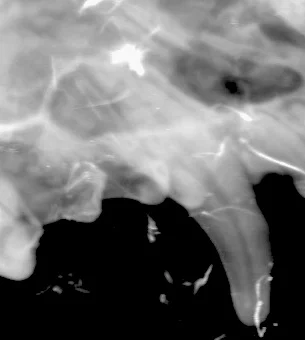

The first thing we did was to take some xrays of his teeth. We needed to confirm that there was no evidence of any infection getting into the tooth through the damaged tooth.

Apart from the missing enamel the teeth appeared healthy.